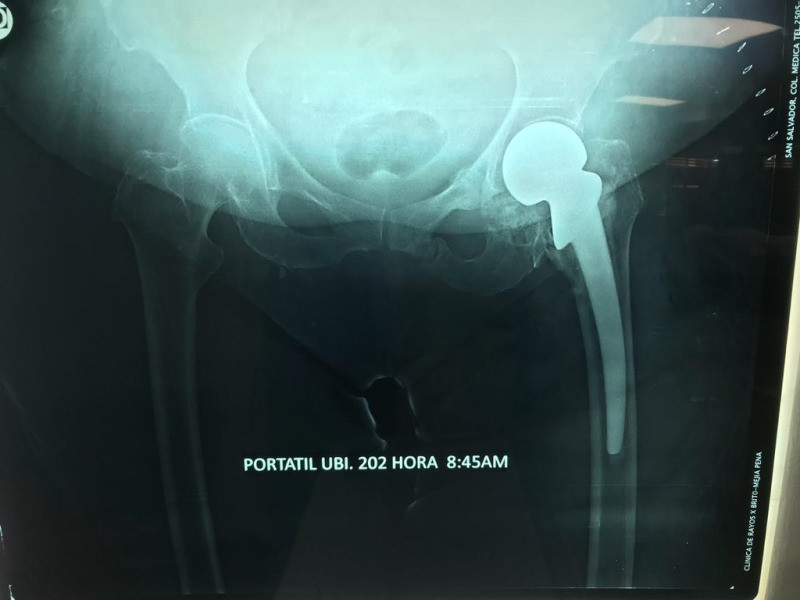

Imágenes de ortopedia y traumatología

Envíado por Dr. José Israel Flores Hernández